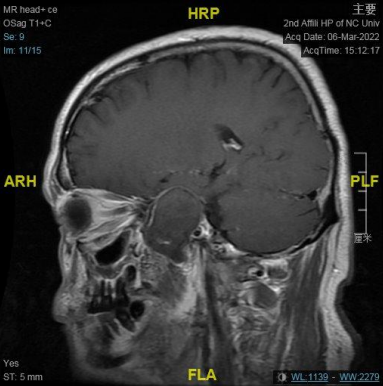

右侧中颅窝鞍旁见一大小约 34 mm✕40 mm✕47 mm 肿块,信号混杂,T1、T2 均呈等低高混杂信号,DWI 呈不均匀混杂信号,边缘包膜呈稍长 T1 短 T2 信号,肿块边界清;肿块无强化,边缘包膜呈明显强化。

结合此病例影像学特点:T1、T2 均呈等低高混杂信号,肿块边界清;肿块无强化,边缘包膜呈明显强化。

从 MRI 增强扫描上肿块无强化,可与神经鞘膜瘤相鉴别;CTA 成像无强化环及强化结节表现,肿块将颈内动脉向后推挤,MRI 增强也无病变周边高信号环及典型的动脉搏动伪影表现,这些影像学表现上可与动脉瘤相鉴别。